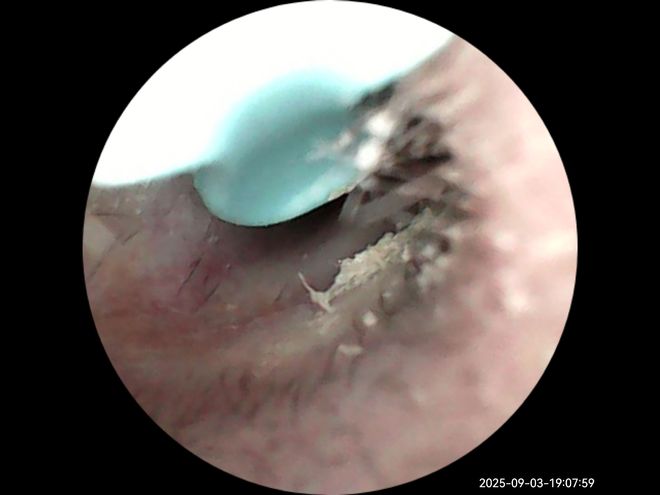

提到可视化,说下西圣Find X跟杂牌耳勺的区别,也是选它的第二大原因。西圣Find X采用1500W像素的内窥镜, 同时有多层光学镀膜镜组,成像清晰、透光率高、色彩还原度高。另外西圣自研了A-Zoom2.0动态调焦系统,说人话就是你掏耳朵即便手再抖,成像都是清晰的,不会糊掉,看得清,清理起来也放心。

最后,搭配专门的App,你还能在掏耳朵的同时录像、拍照,时刻能记录耳道状况。耳朵不舒服时,直接探进耳道查看一下,发炎、耳膜破裂、耳结石等等一看便知。